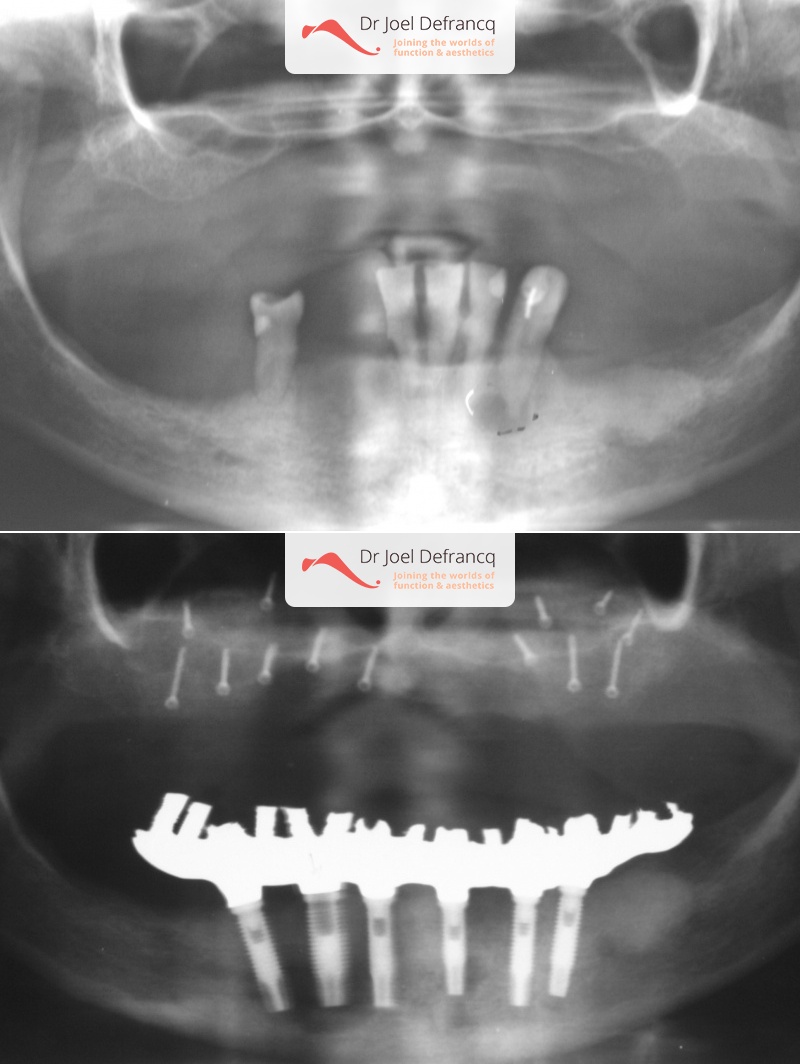

Dentale diagnose

- Open beet

Behandeling tandheelkundige implantaten

- Vaste tanden op implantaten (bovenkaak)

- Vaste tanden op implantaten (onderkaak)